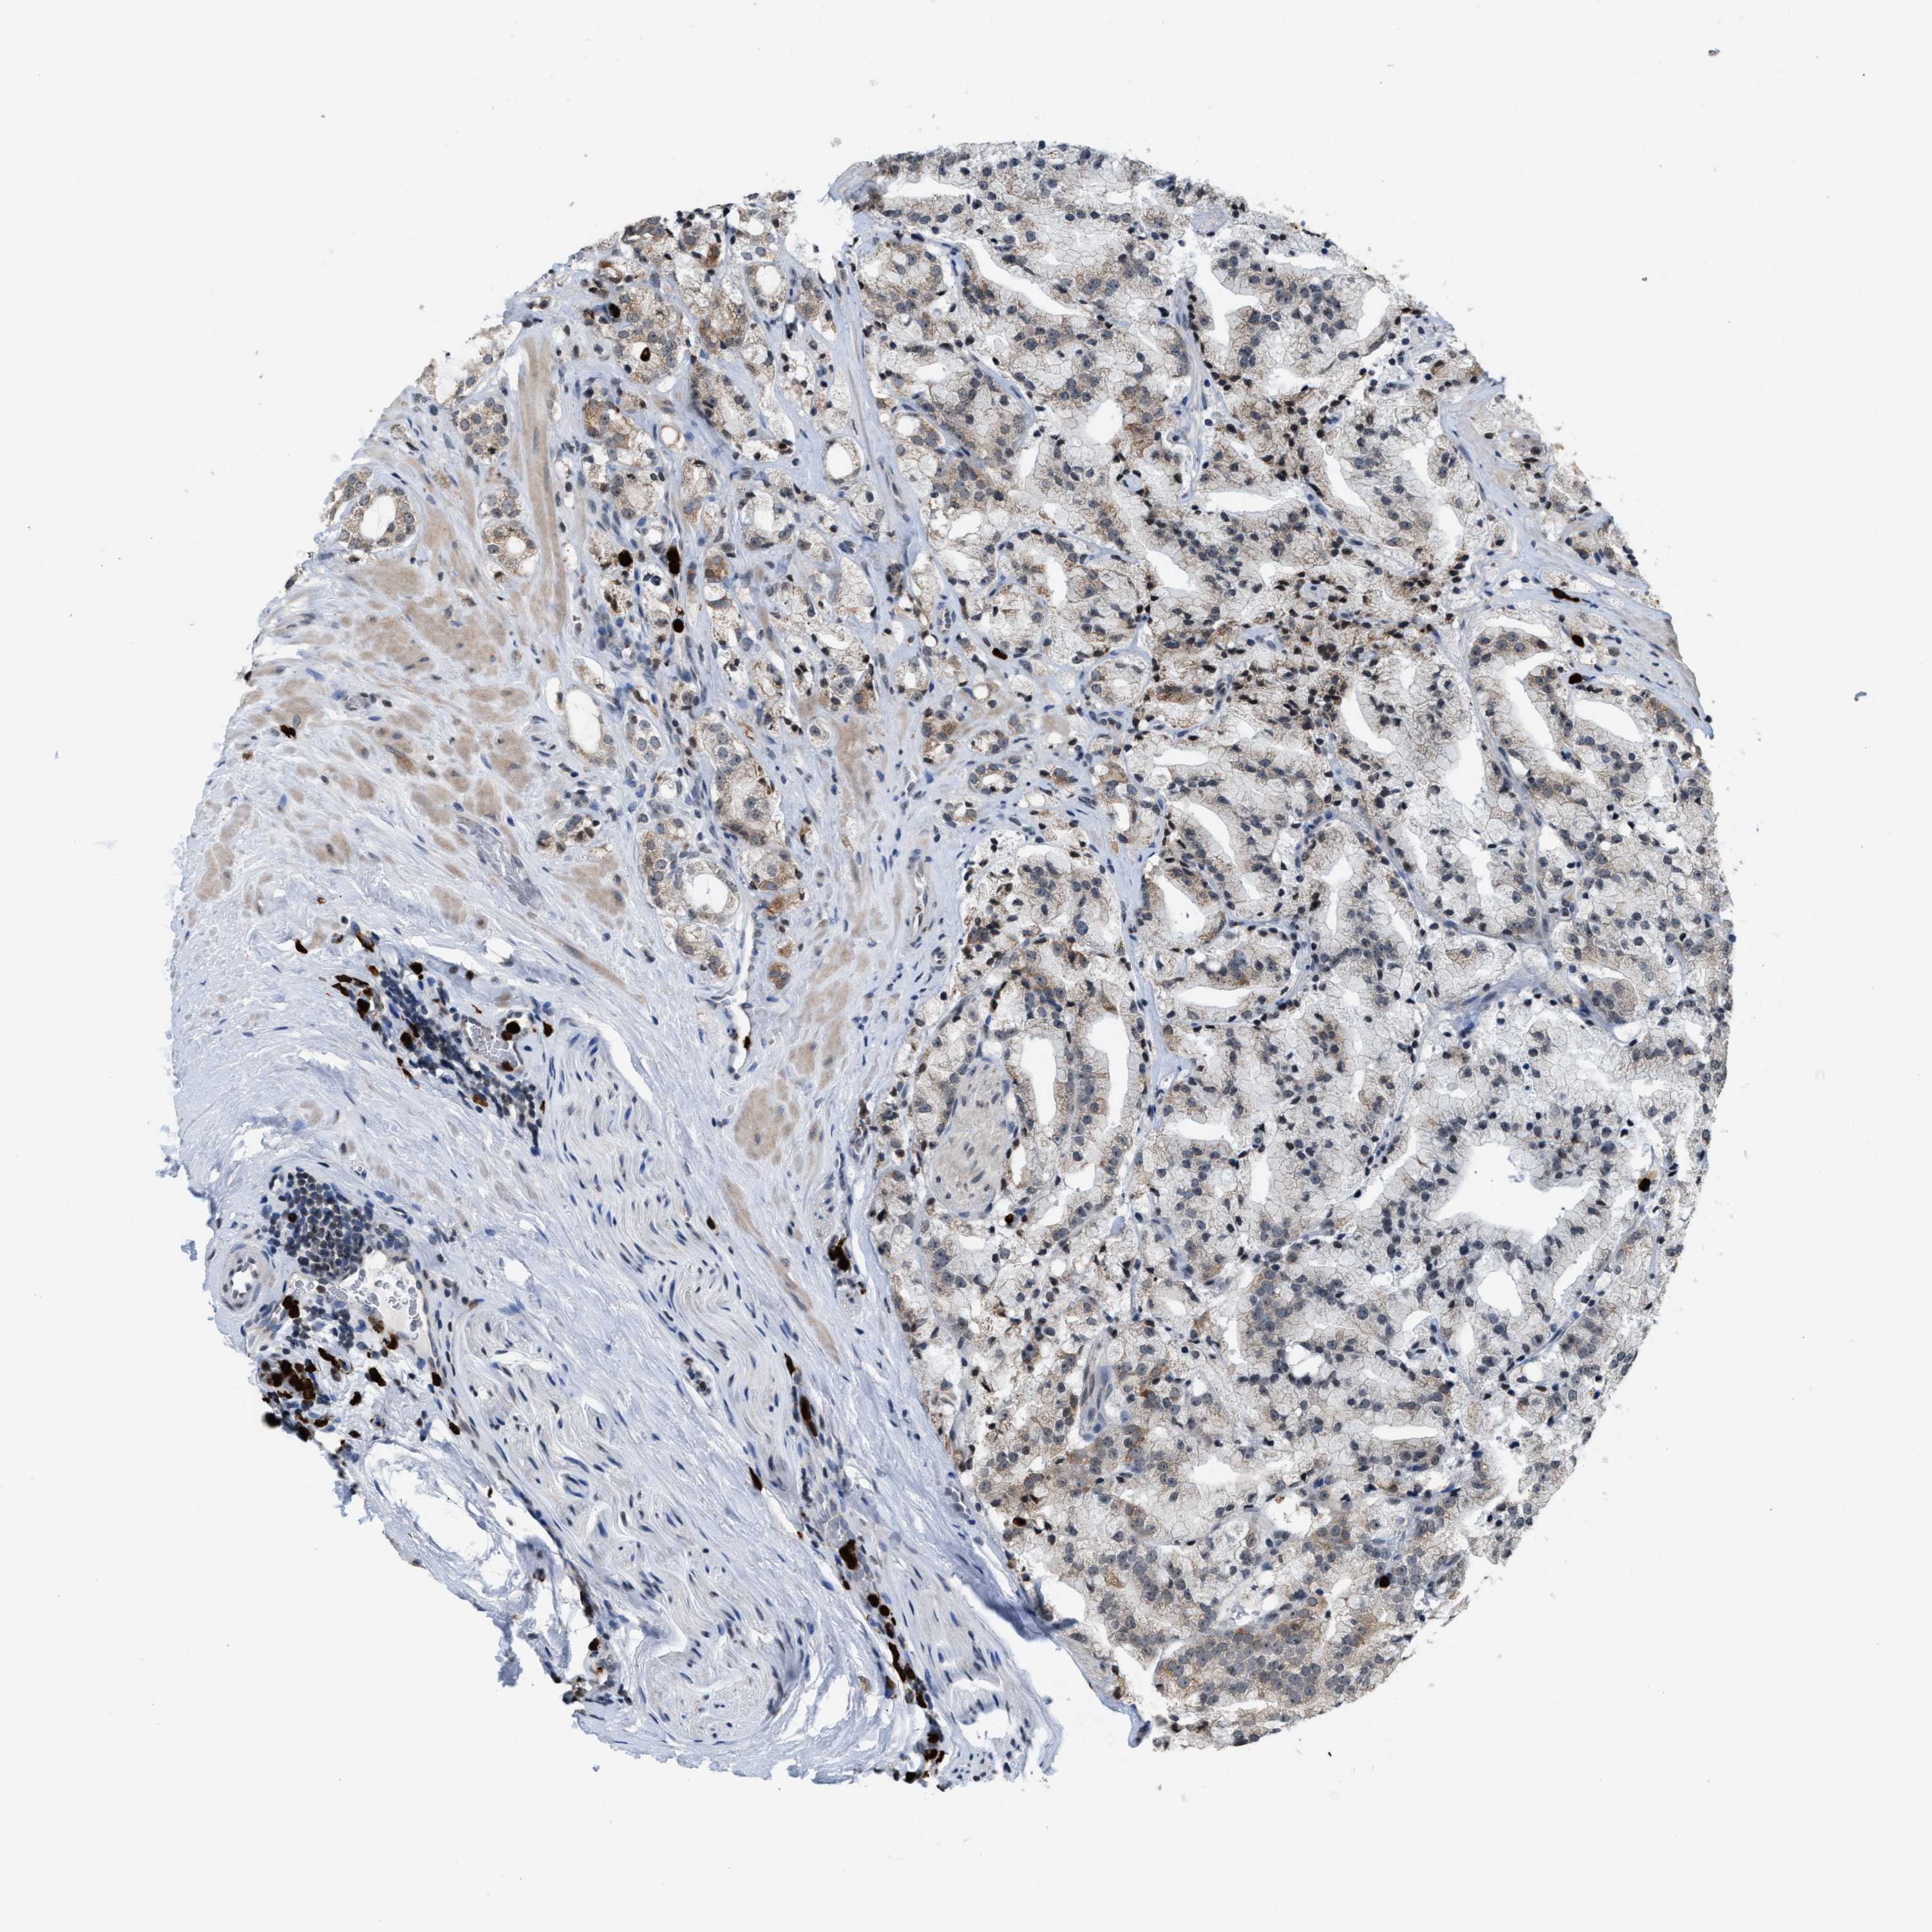

PROSTATE CANCER - Protein expressioni

A mouse-over function shows sample information and annotation data. Click on an image to view it in a full screen mode. Samples can be filtered based on level of antibody staining by selecting one or several of the following categories: high, medium, low and not detected. The assay and annotation is described here.

Note that samples used for immunohistochemistry by the Human Protein Atlas do not correspond to samples in the TCGA dataset.

Antibody stainingi

Antibody staining in the annotated cell types in the current human tissue is reported as not detected, low, medium, or high, based on conventional immunohistochemistry profiling in selected tissues. This score is based on the combination of the staining intensity and fraction of stained cells.

Each image is clickable and will lead to virtual microscopy that enables deeper exploration of all samples and also displays staining intensity scores, fraction scores and subcellular localization as well as patient and tissue information for each sample.

Antibody HPA022470

Antibody HPA031079

Staining

High

Medium

Low

Not detected

Intensity

Strong

Moderate

Weak

Negative

Quantity

>75%

75%-25%

<25%

None

Location

Nuclear

Cytoplasmic/membranous

Cytoplasmic/membranous,nuclear

Adenocarcinoma, High grade

Adenocarcinoma, Low grade